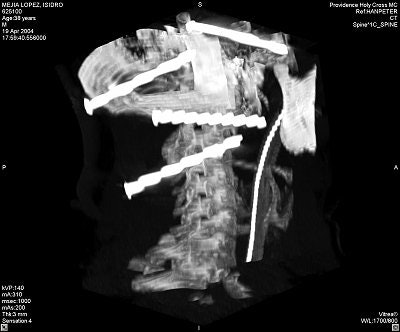

Quinonez was able to remove the nails based on the angiogram and 3D CT reconstructions that showed the location of the nail heads -- most critically, the head of a nail that had entered anteriorly through the base of the skull into the face and that now rested medial to the mandibular condyle (images C-E below).

![]() |

Image C.

"There was concern as to (a nail's) relationship to several branches of the carotid artery," noted Greenberg. "The nail was going to be taken out from the left side of his neck, but the sharp end was on the right side, where the surgeon was not going to have access if something was going to start bleeding."